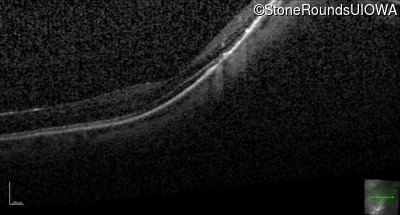

Age at visit: 41 years (Visit 2)

OD OS

This 41 year old woman was highly myopic as a child and experienced a rhegmatogenous retinal detachment OS at age 20.

Refraction OD:     -17.25 +1.00 x 93

Refraction OS:     -18.25 +3.50 x 56